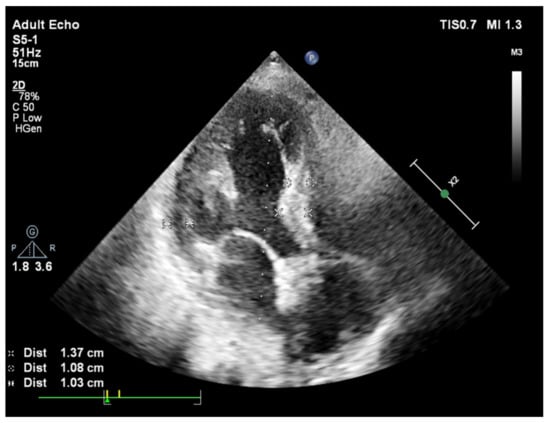

2. Basal Septal Hypertrophy and Clinic Observations

3. BSH and Animal Validation Studies

4. Heart Failure with Preserved Ejection Fraction